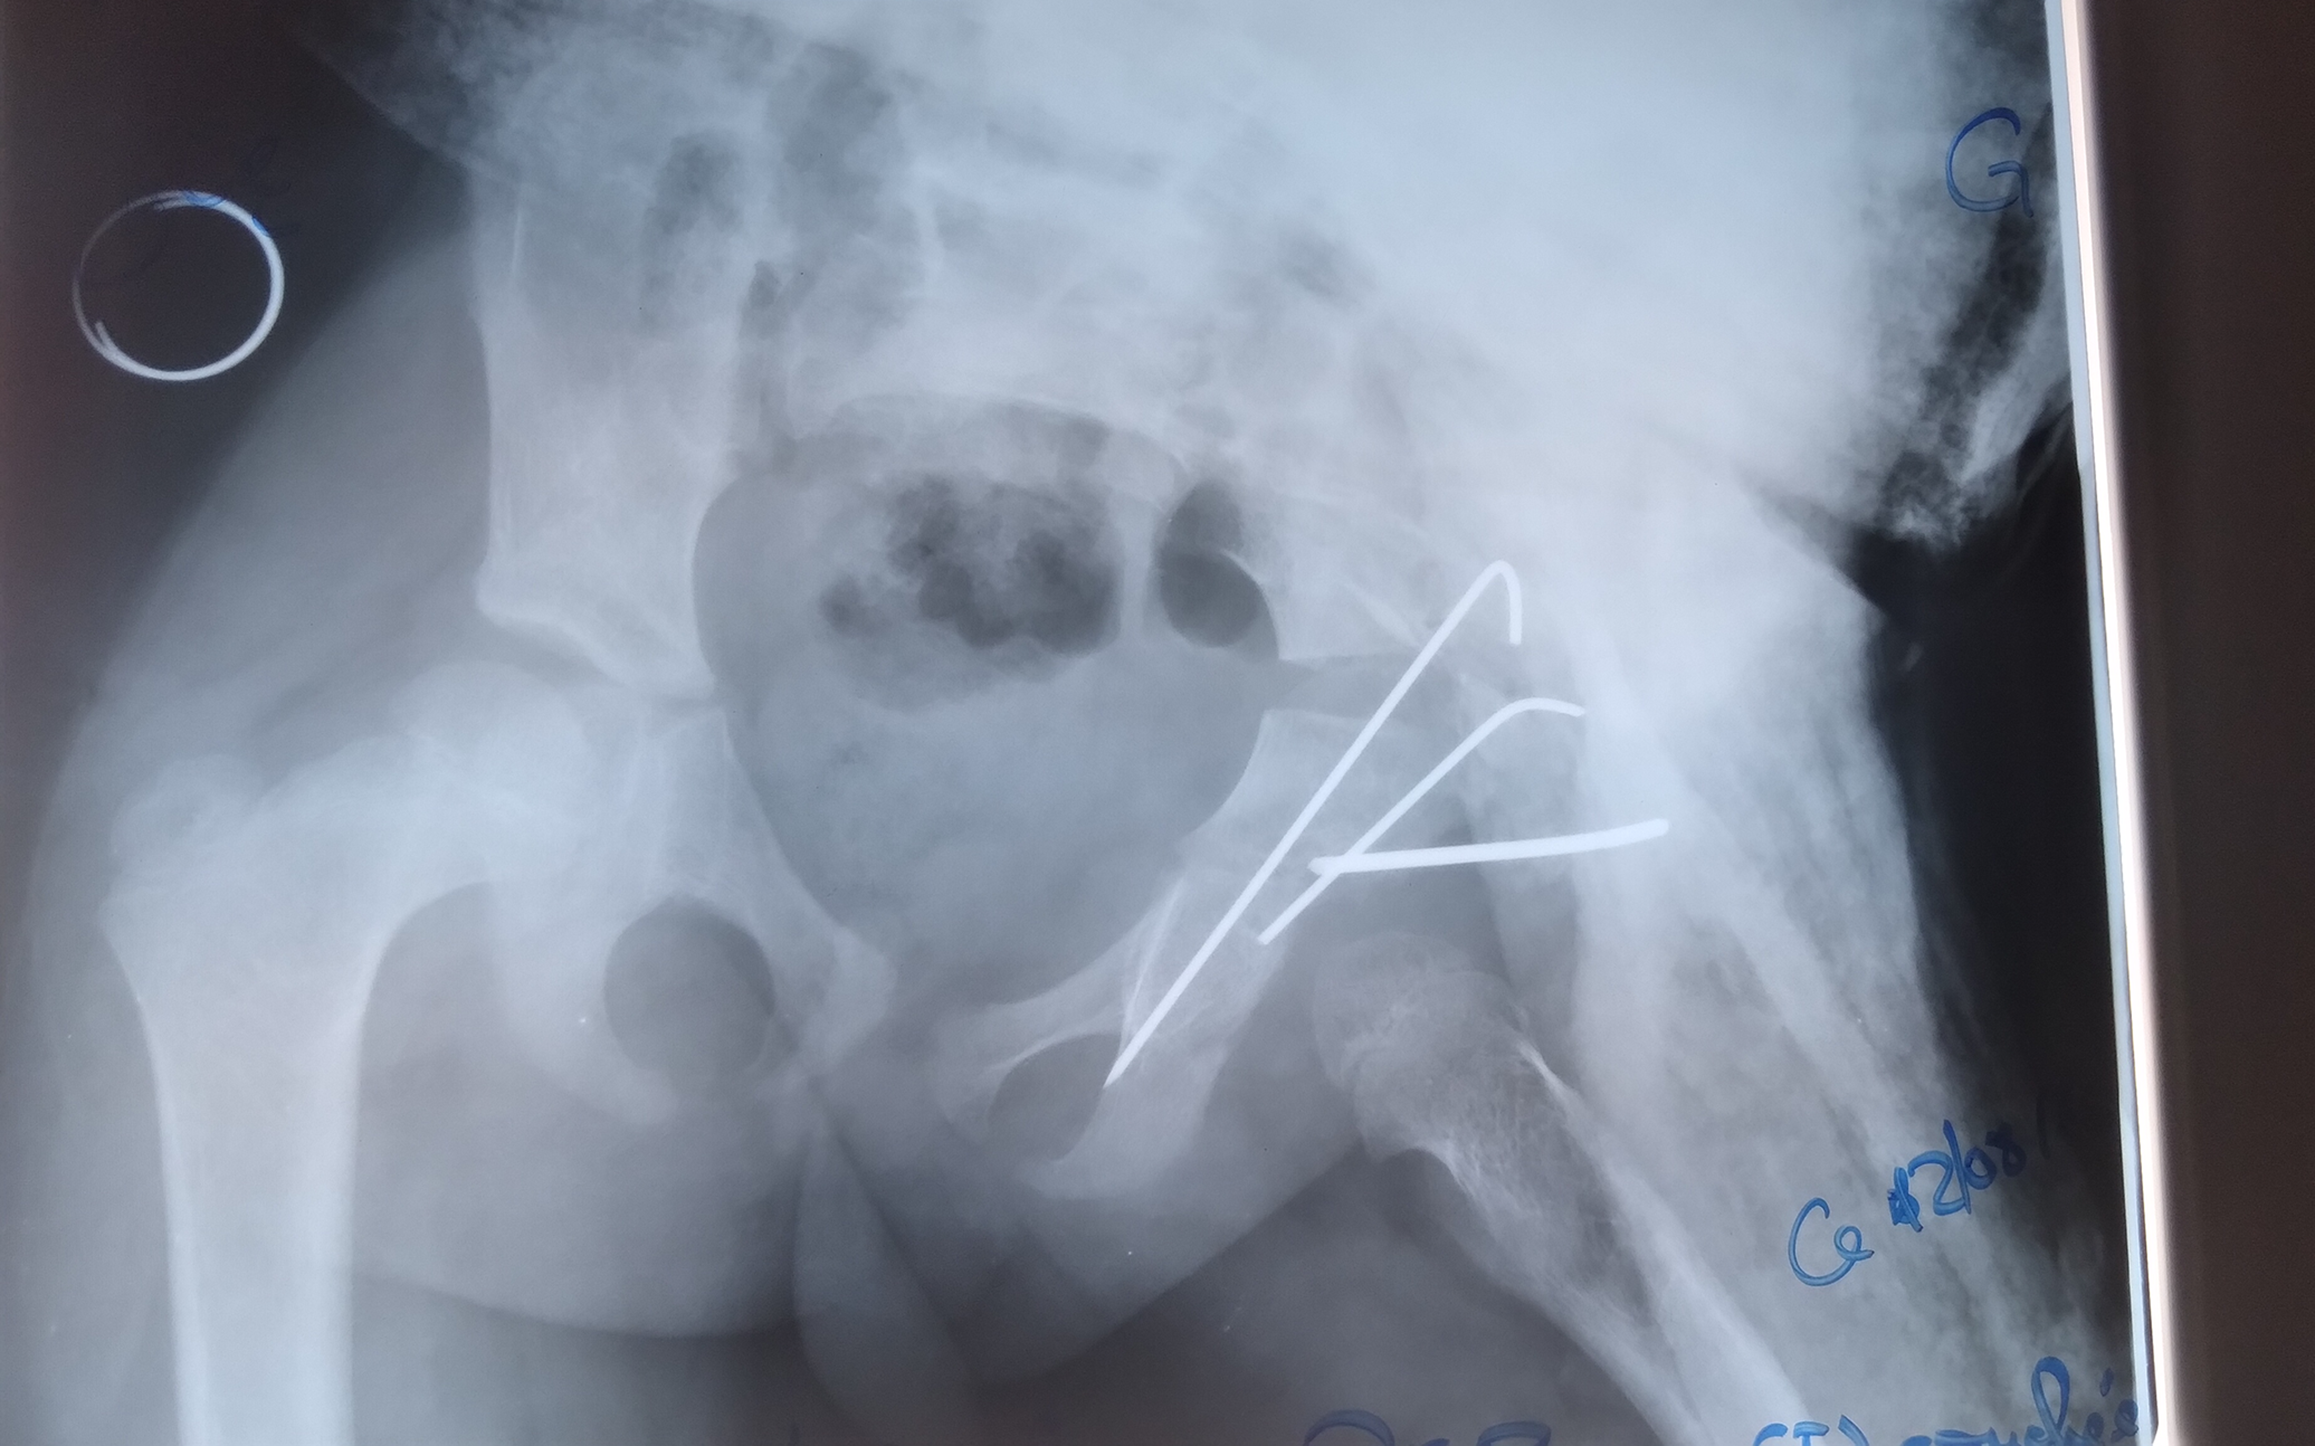

Radiological outcomes were assessed using the Severin classification. Each child underwent a mean of four radiographs during the treatment course. At final follow-up, 22 hips (84.6%) were classified as Severin stage I or II, indicating concentric and congruent reduction. Three hips (11.5%) showed residual dysplasia without subluxation. One case of redislocation (Severin stage V) was observed in a 21-month-old child with a unilateral Tönnis stage IV DDH, initially managed with 2 months of adhesive traction followed by spica casting. This required re-hospitalization and repeat treatment with traction and PPC. No further complications occurred (Figures 2 and 3).

Orthopedic treatment: Initial treatment consisted of continuous skin traction using adhesive bands fixed to both lower limbs. The patient was positioned supine, with the hips in extension and slight abduction, and the traction angle ranged from 10° to 30° from the bed plane (Figure 1). Traction force ranged from 10% to 50% of body weight depending on the degree of femoral head displacement. Radiographs were obtained every 15 days to assess reduction and adjust traction in abduction and/or internal rotation. Once the femoral head was centered, traction was followed by the application of a pelvipedal cast (PPC) under general anesthesia and fluoroscopic guidance. The cast was maintained for 2 to 4 months. This sequence was applied to all patients as definitive treatment or to prepare soft tissue for surgery.